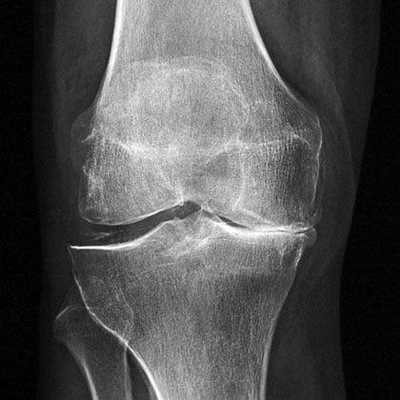

Динамика болезни на рентгене.

Откладывать хирургию при гонартрозах 3-4 степени чревато деформацией позвоночника. Это происходит из-за хромоты. Дегенеративные процессы артроза глубоко затронут кости, из-за чего они приобретут хрупкость, потеряют плотность и зафиксировать к ним компоненты импланта станет сложно.

Артроз коленного сустава на рентгене.

Показания к замене

Посмотрите на рентген, на нем вы видите, до какой степени при запущенном гонартрозе изношен гиалиновый хрящ, обеспечивающий гладкое скольжение суставных поверхностей. Концевые участки костей грубо деформируются нарушая функции сгибания и разгибания конечности вызывая интенсивный болевой синдром.